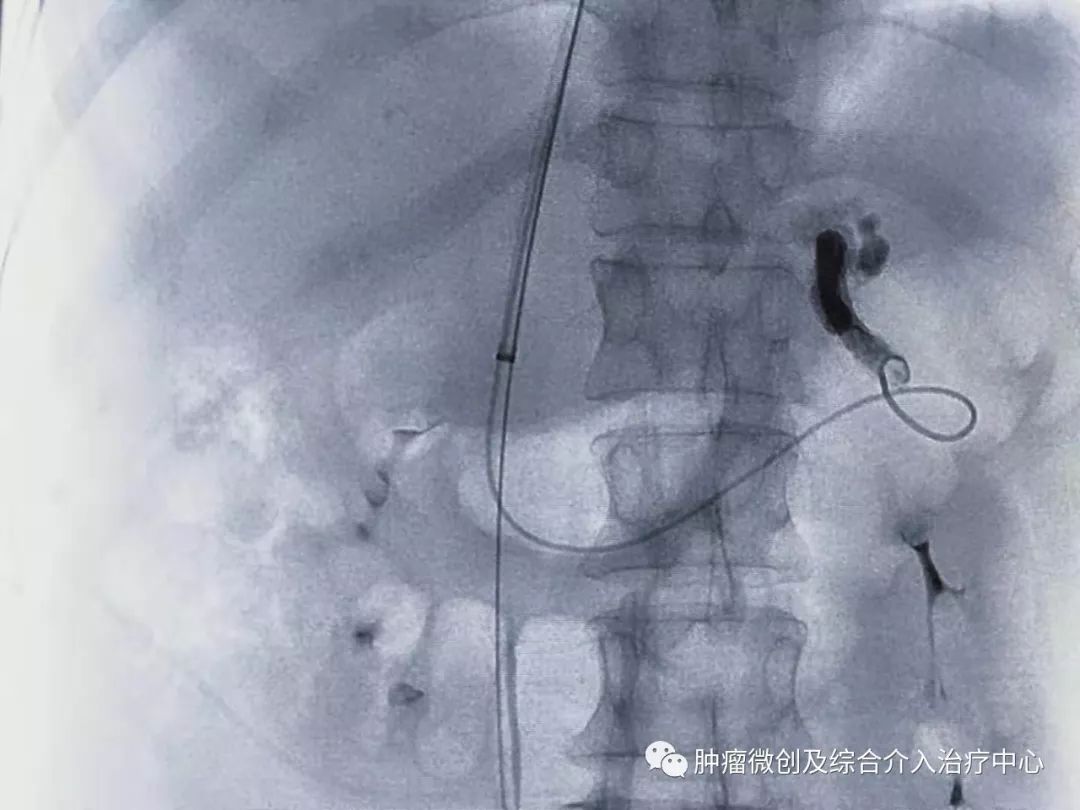

再次造影可见:门脉血流流向-体静脉达到分流目的,术前侧压力42,术后25,门脉压力明显降低,达到防止再次出血目的。